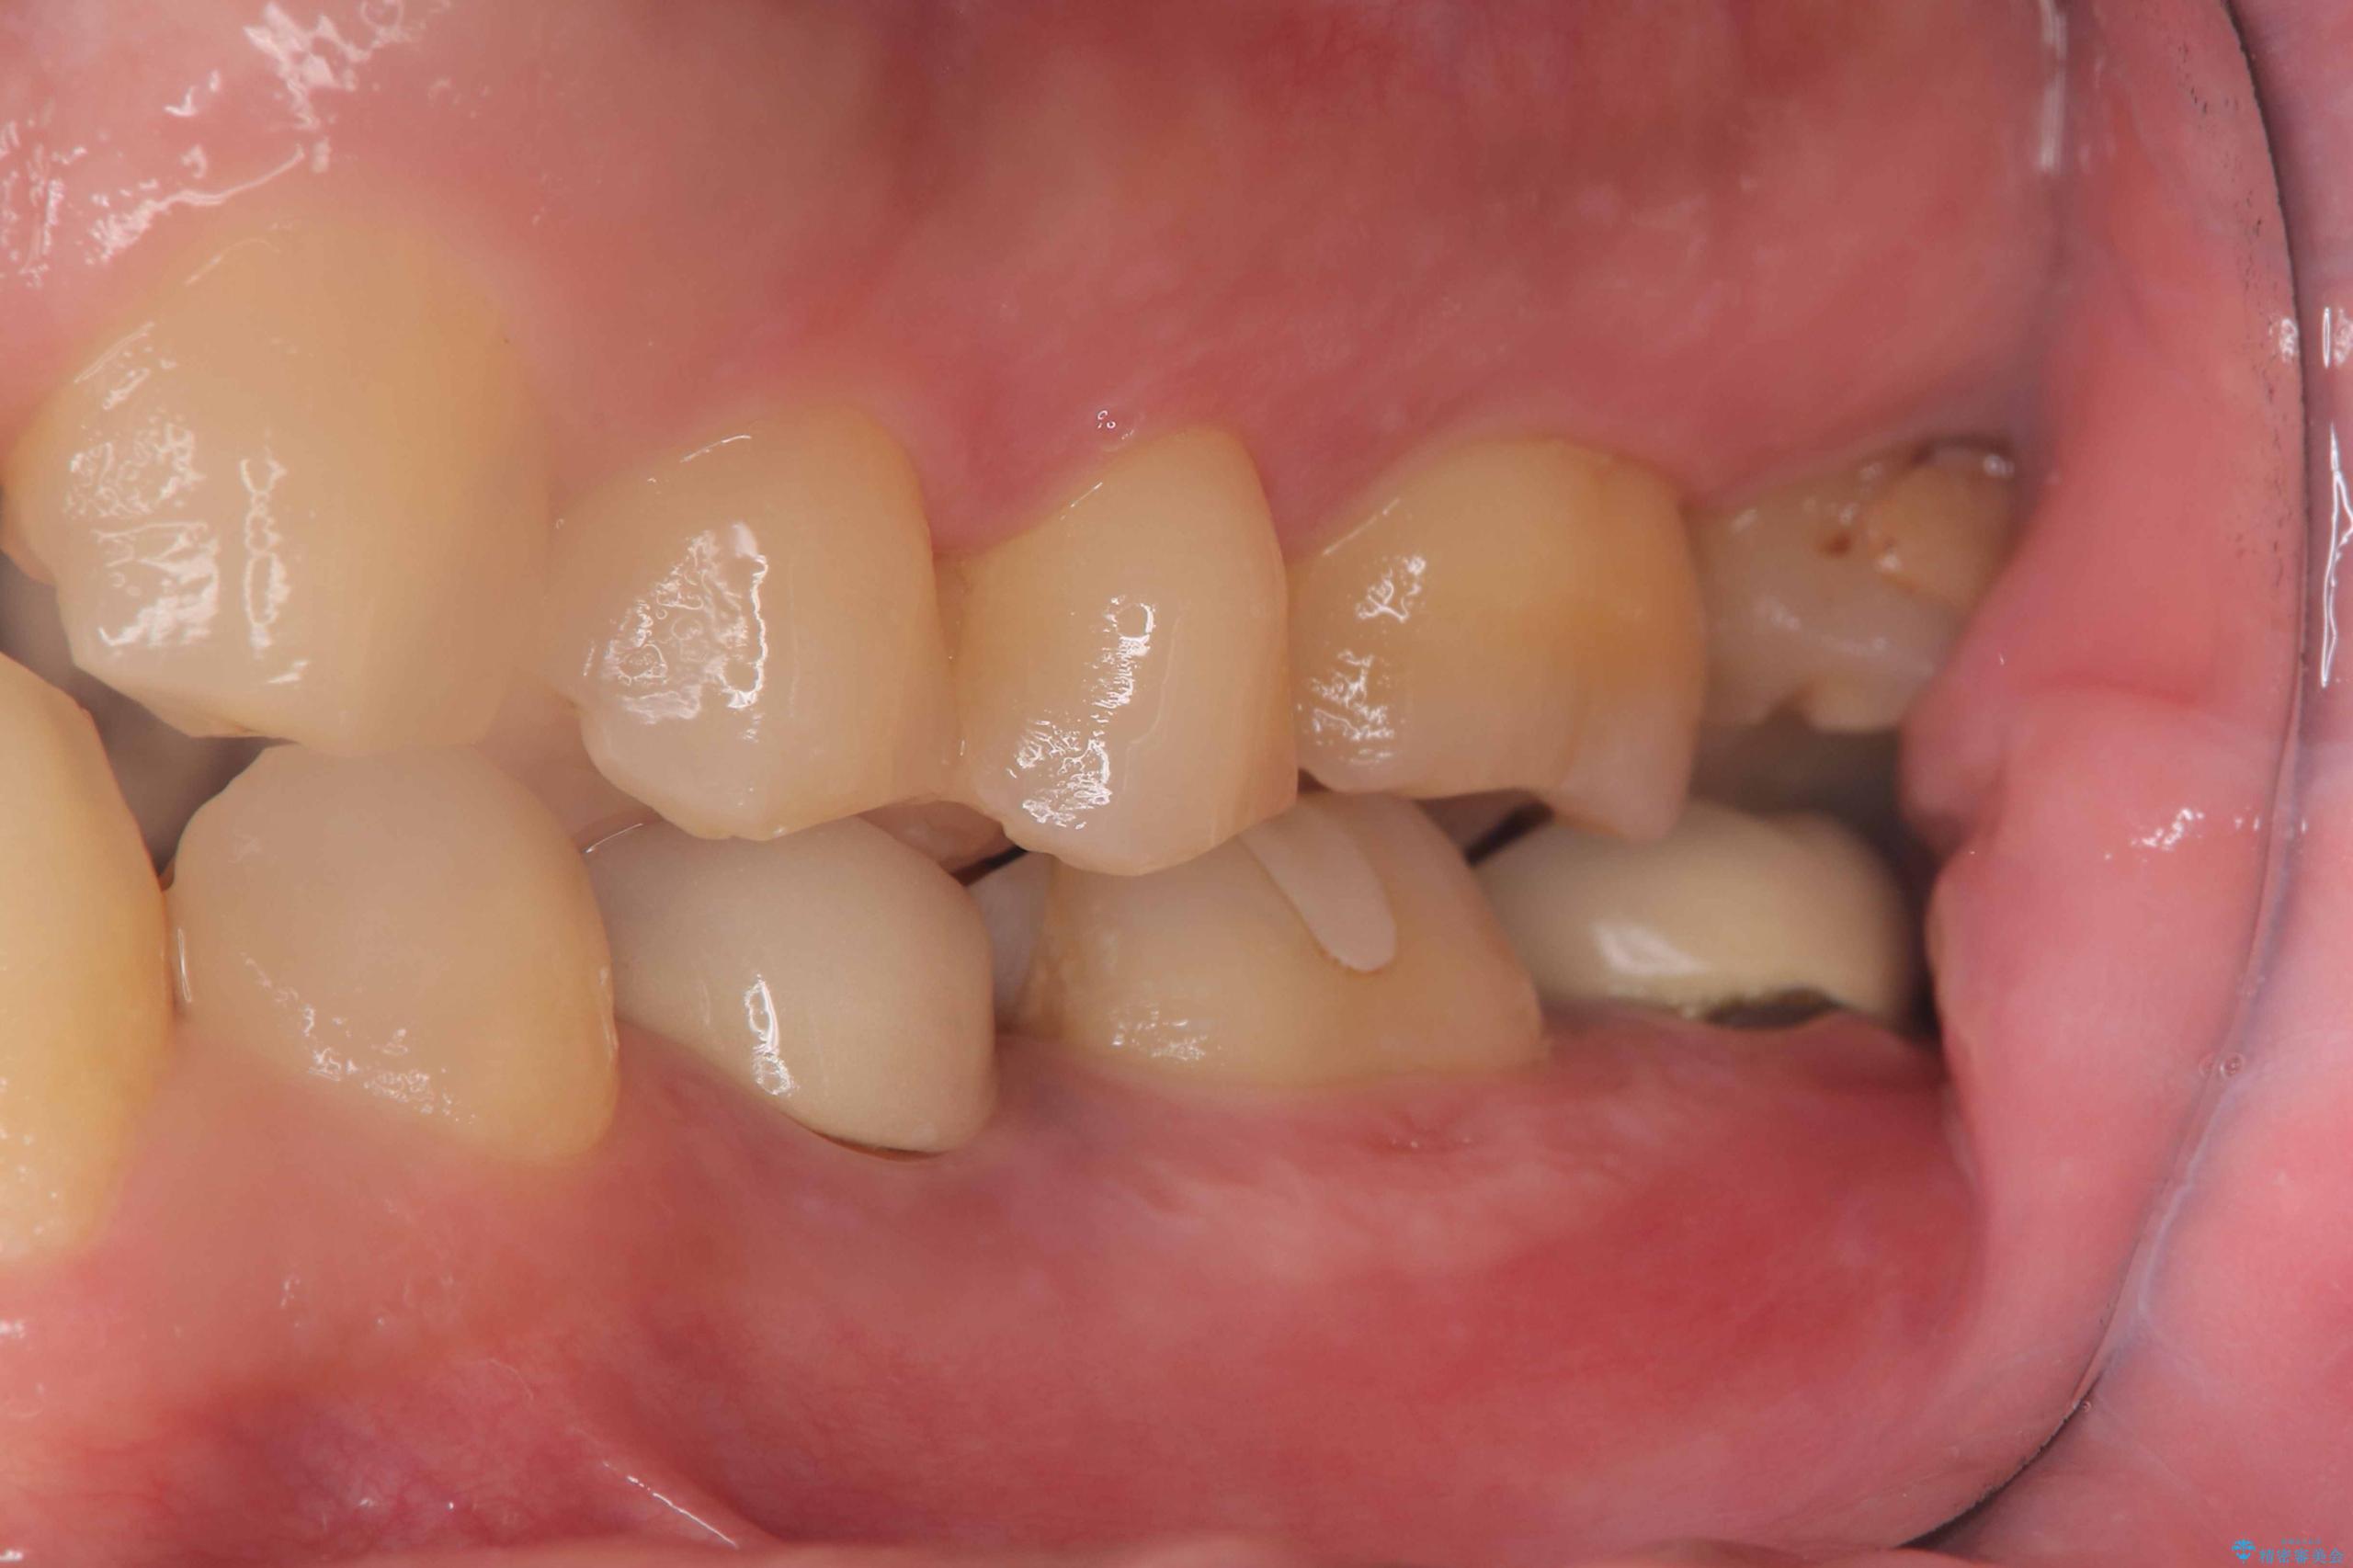

- 過去にヘミセクションが行われていたと思われる左下7番は、大きな歯根嚢胞および根尖病変が認められ、さらに骨縁下カリエスを伴っており、歯肉には瘻孔が形成されている状態でした。

保存は困難と判断し、左下7番は抜歯即時インプラントによる治療を行いました。

また、左下6番には形態が不自然で適合不良のセラミックインレーが装着されていたため、二次カリエスのリスクを考慮し、オールセラミッククラウンによる治療を行いました。